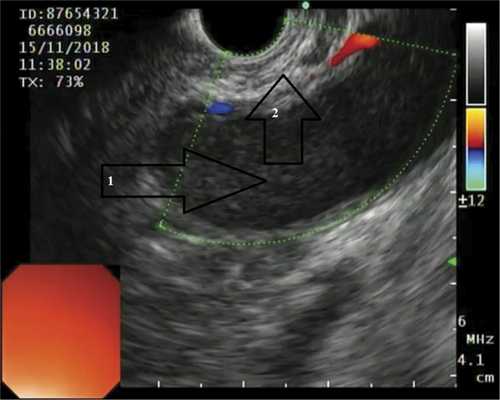

ПК локализовались в теле ПЖ у 7 (30,4%) пациентов, в хвосте ПЖ — у 7 (30,4%), в головке ПЖ — у 6 (26,2%) (рис. 1). Рис. 1. Псевдокиста головки поджелудочной железы (изображение при ультразвуковом исследовании). Стрелками указаны полость псевдокисты (1), бессосудистая зона (2). The arrows indicate pseudocyst cavity (1), avascular zone (2). У 3 (1%) больных имело место сочетанное расположение ПК в головке и теле ПЖ.